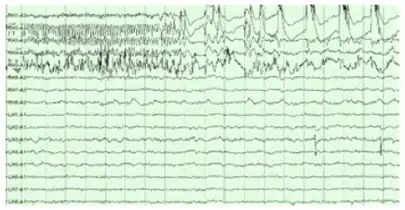

Electroencephalography

The hippocampus shows two major "modes" of activity, each associated with a distinct pattern of neural population activity and waves of electrical activity as measured by an electroencephalogram (EEG). These modes are named after the EEG patterns associated with them: theta and large irregular activity (LIA). The main characteristics described below are for the rat, which is the animal most extensively studied.[80]

The theta mode appears during states of active, alert behavior (especially locomotion), and also during REM (dreaming) sleep.[81] In the theta mode, the EEG is dominated by large regular waves with a frequency range of 6 to 9 Hz, and the main groups of hippocampal neurons (pyramidal cells and granule cells) show sparse population activity, which means that in any short time interval, the great majority of cells are silent, while the small remaining fraction fire at relatively high rates, up to 50 spikes in one second for the most active of them. An active cell typically stays active for half a second to a few seconds. As the rat behaves, the active cells fall silent and new cells become active, but the overall percentage of active cells remains more or less constant. In many situations, cell activity is determined largely by the spatial location of the animal, but other behavioral variables also clearly influence it.

The LIA mode appears during slow-wave (non-dreaming) sleep, and also during states of waking immobility such as resting or eating.[81] In the LIA mode, the EEG is dominated by sharp waves that are randomly timed large deflections of the EEG signal lasting for 25–50 milliseconds. Sharp waves are frequently generated in sets, with sets containing up to 5 or more individual sharp waves and lasting up to 500 ms. The spiking activity of neurons within the hippocampus is highly correlated with sharp wave activity. Most neurons decrease their firing rate between sharp waves; however, during a sharp wave, there is a dramatic increase in firing rate in up to 10% of the hippocampal population